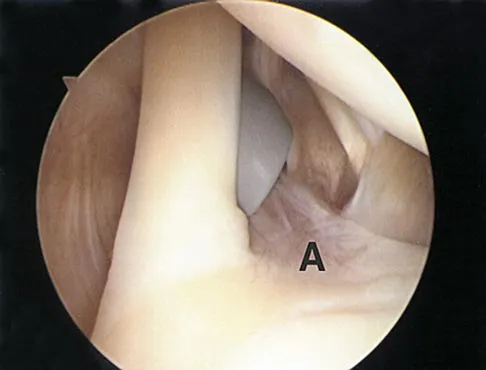

In the arthroscopic photograph shown in Figure 5, the structure labeled "A" functions primarily as a restraint to translation of the humeral head in what direction?

Explanation

The superior glenohumeral ligament identified as "A" in the figure functions primarily as a restraint to inferior glenohumeral translation of the adducted arm. The middle glenohumeral ligament is highly variable and pooly defined in up to 40% of the population and functions to restrain anterior translation of the externally rotated arm in the midrange of abduction. The anterior band of the inferior glenohumeral ligament is the primary restraint to anterior/inferior translation of the head with the shoulder abducted to 90 degrees and in maximum external rotation. Ticker JB, Bigliani LU, Soslowskiy LJ, et al: Inferior glenohumeral ligament: Geometric and strain-rate dependent properties. J Shoulder Elbow Surg 1996;5:269-279.